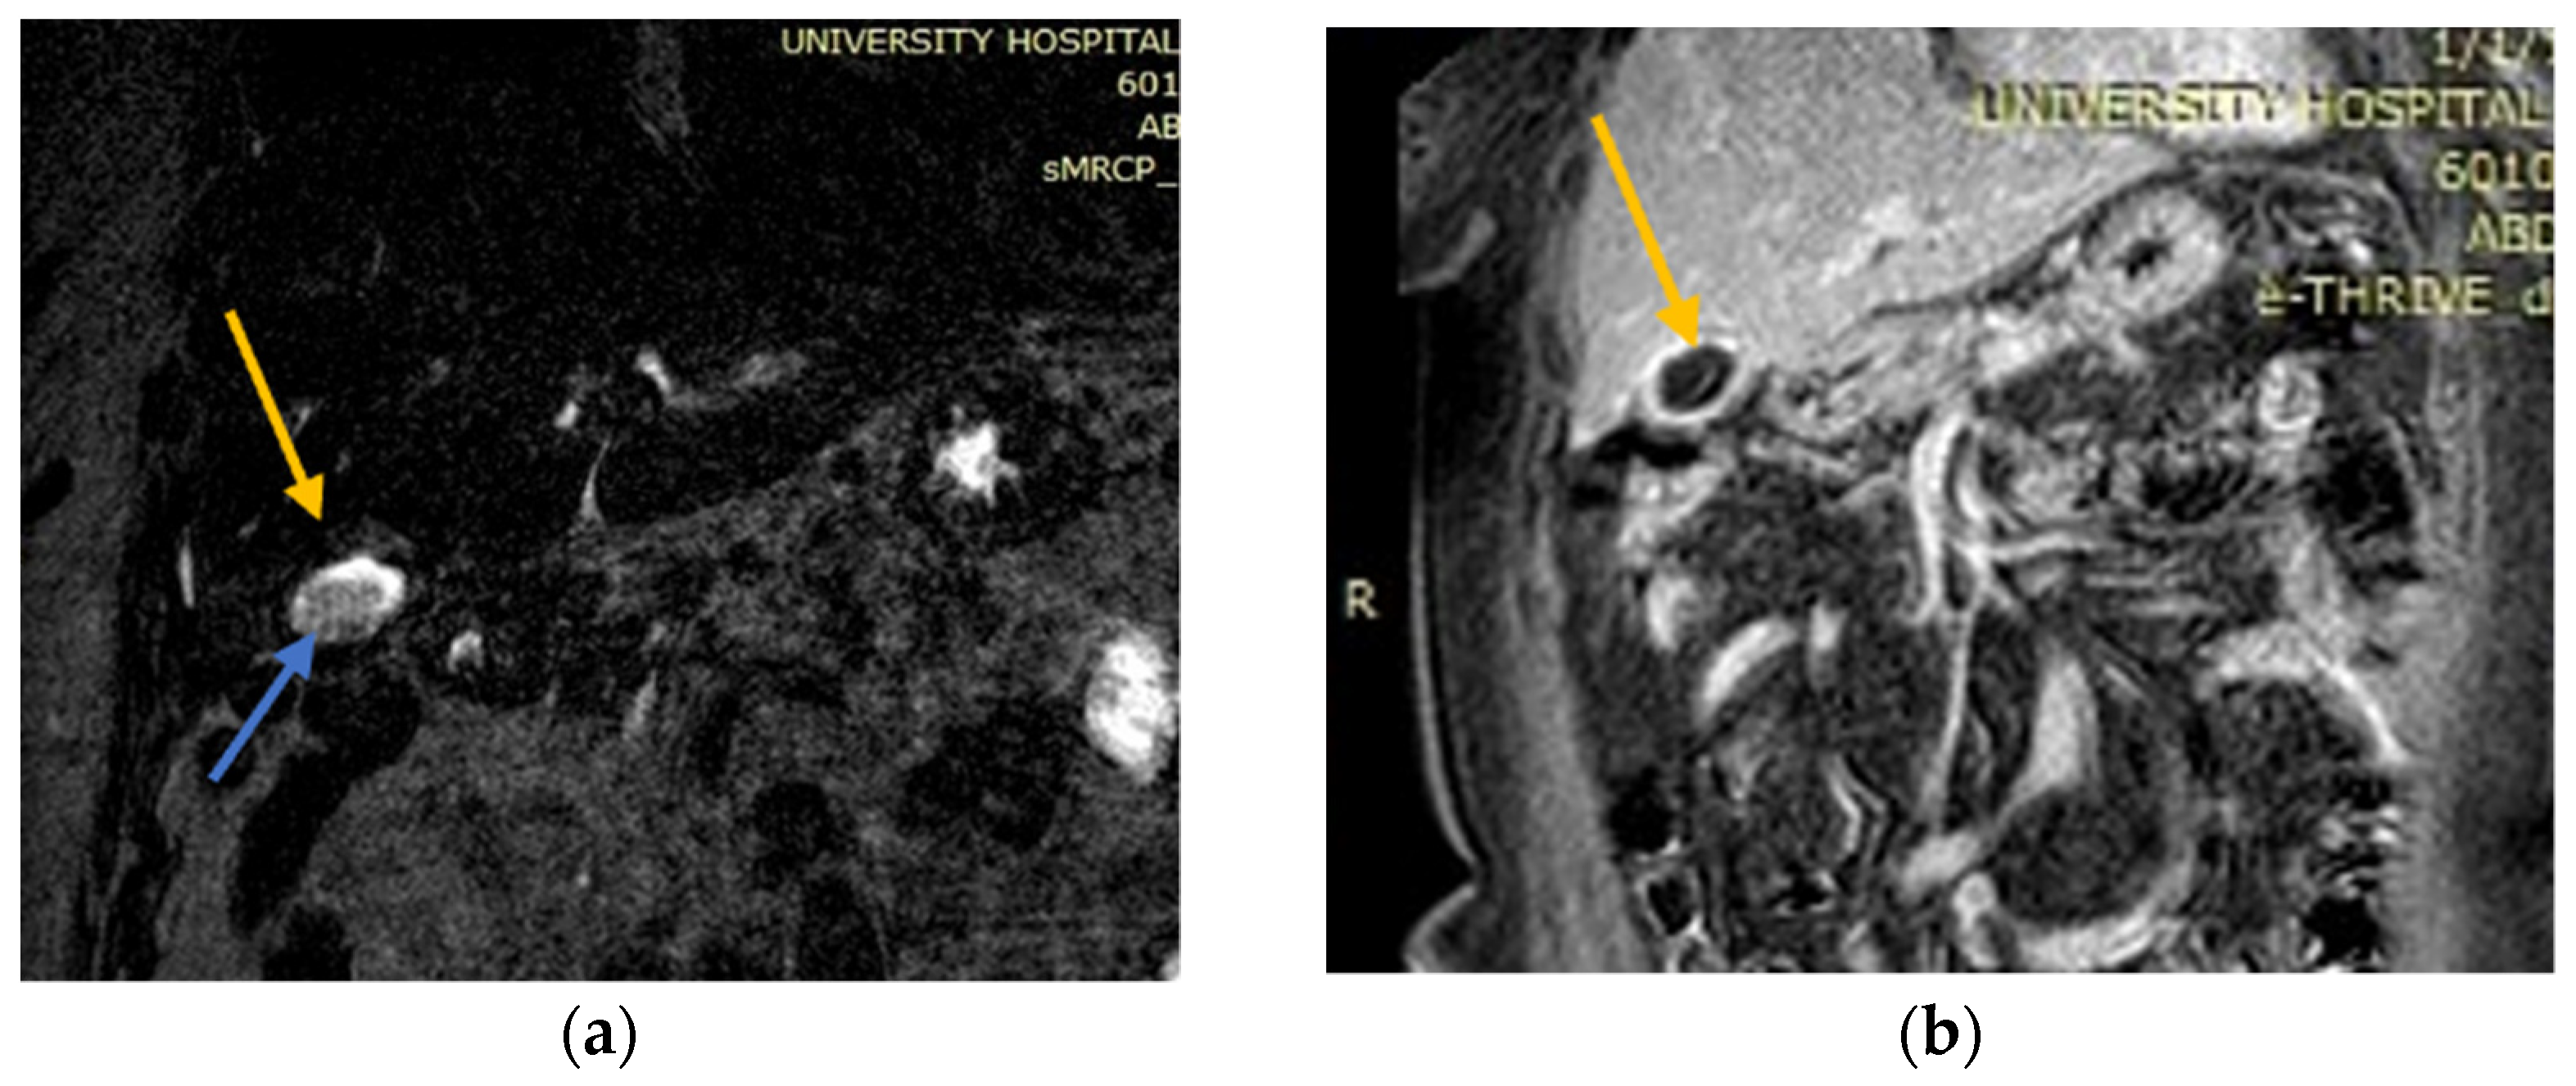

2.1. Case 1

2.2. Case 2